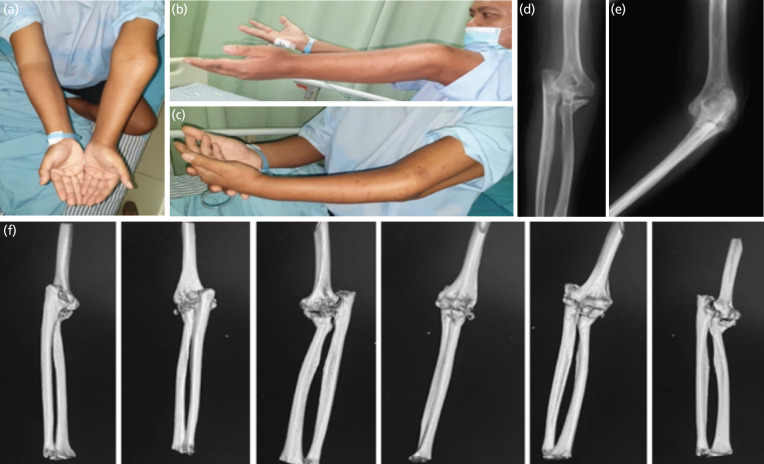

In young patients, the use of total elbow arthroplasty (TEA) is rarely preferred due to its high rate of mechanical failure. Poor compliance and psychological problems encountered may lead to increased difficulty in management. A 38-year-old male complained stiffness and pain on his left elbow. History of trauma was present 10 months ago, when he fell down from a tree of 6m high. Immediate closed reduction and immobilisation with backslab was performed, but he was lost to follow-up due to Schizophrenia. In physical examination, we found varus and recurvatum deformity with inability to flex the elbow beyond 30° and perform pronation. Plain radiograph and CT scan confirmed the terrible triad of elbow with callus formation. Total elbow arthroplasty with soft tissue release was then performed, resulting in satisfactory range of motion at one year follow-up. The management of neglected terrible triad of the elbow is challenging not only due to the bony problems, but also contracted muscles and fibrotic joint. TEA previously has been described in cases of inflammatory arthritis and degenerative arthritis, less in post-traumatic conditions especially in young patients. Though there is still scarcity in literatures discussing the burden of psychiatric problems in arthroplasty patients, but the existing literatures proved the correlation between psychiatric comorbidity with higher rate of post-operative adverse events. Total elbow arthroplasty can be considered as a surgical treatment for a young patient with neglected fracture dislocation of elbow with satisfactory result; however close post-operative monitoring and routine physiotherapy exercise should always be performed.